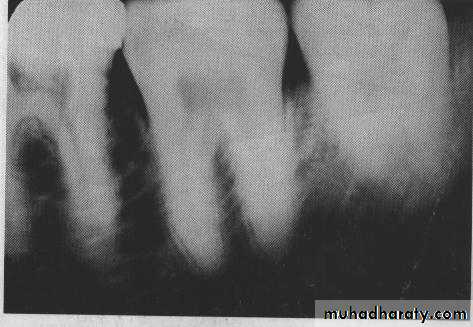

a. Subject thickness :The thicker the subject (greater tissue thickness), the more the beam is attenuated and the lighter the resultant image .Large patients with greater tissue thickness will required longer exposure time or increased milliamper setting.b. Object density : Denser objects (strong absorbers such as bone, ,enamel,dentin,cementum,restoration) cause the radiographic image to be light and are said to be radiopaque. Objects with low densities are weak absorbers.They allow most photons to pass through, and they cast a dark area on the film that corresponds to the radiolucent object.